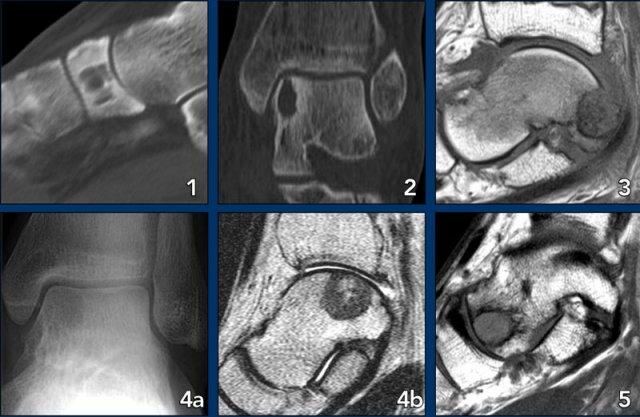

1. Ewing sarcoma in the calcaneus

2. Glomus tumor

3. Same patient MRI